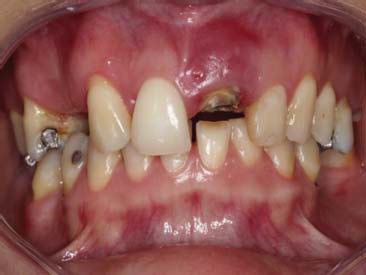

A paciente ERL, gênero feminino, 28 anos, procurou atendimento relatando dor na região anterior superior, com histórico de trauma prévio durante a mastigação. Na avaliação da paciente, o dente 21, aonde havia uma coroa cerâmica instalada com núcleo metálico, apresentava uma fratura obliqua, gengiva edemaciada, com sinais clínicos de infecção na parede vestibular do alvéolo (figura 1 e figura 2). O plano de tratamento incluiu a indicação de exodontia do dente 21, seguida de um implante imediato (Straumann® Bone Level SLActive) associado a um cicatrizador personalizado para manter a caracterização do contorno gengival do elemento.